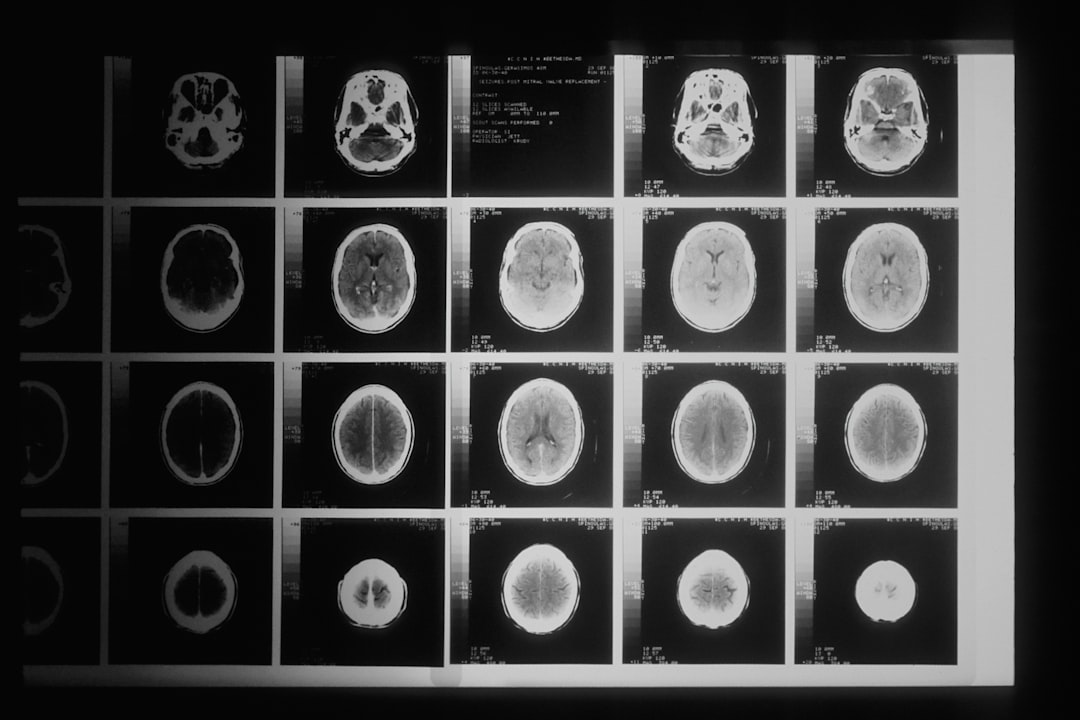

오상신경외과는 척추 치료의 최전선에서 환자들에게 최상의 의료 서비스를 제공하고 있습니다. 최신 척추 치료법을 도입하여, 많은 환자들이 고통에서 벗어나 건강한 삶을 되찾을 수 있도록 도움을 주고 있습니다. 파주 오상신경외과는 전문 의료진과 현대적 장비를 통해, 치료의 정확성을 높이고 있습니다. 이러한 노력이 환자들에게 큰 신뢰를 얻고 있는 이유입니다.

최근의 척추 치료법은 과거의 방법들과 비교했을 때 많은 발전이 있었는데, 전통적인 수술법보다 적은 침습성을 자랑하고 있습니다. 오상신경외과 의원에서는 최소 침습 수술 및 비수술적 치료를 통해, 환자들이 빠르게 회복할 수 있도록 하는 데 중점을 둡니다. 이러한 첨단 치료법은 환자들의 만족도를 크게 향상시킵니다.

오상신경외과에서 진행하는 최신 척추 치료법은 다양한 접근 방식으로 이루어집니다. 비수술적 치료법으로는 물리치료, 도수 치료, 약물 치료 등이 있으며, 수술이 필요한 경우에도 최소 침습 수술이 주로 시행됩니다. 이로 인해 회복 시간이 짧고, 통증이 적은 장점이 있습니다.

특히, 척추 교정 치료나 척추 내시경 수술은 환자들에게 큰 인기를 끌고 있습니다. 오상신경외과의 이러한 치료법은 환자 개개인의 특성을 고려하여 진행되며, 치료 후 빠른 일상 복귀를 가능합니다. 따라서 환자들은 치료에 대한 만족도가 높습니다.